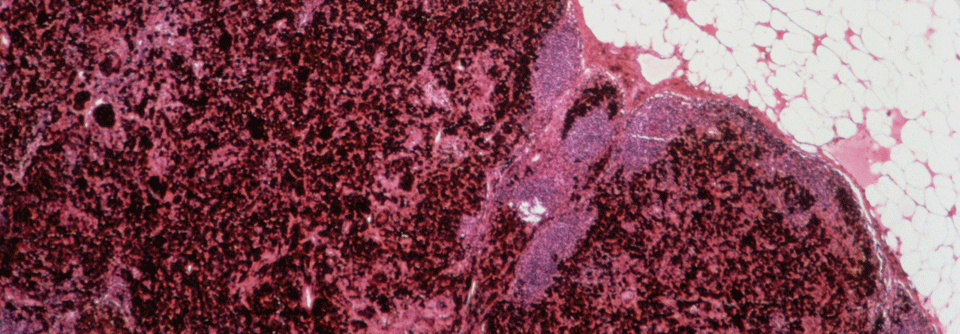

AML

Entscheidung für oder gegen eine alloHSCT hängt von vielen Faktoren ab

Die Abwägung zwischen zu erwartender Verbesserung des krankheitsfreien Überlebens und behandlungsbedingter Mortalität beeinflusst auch heute noch…